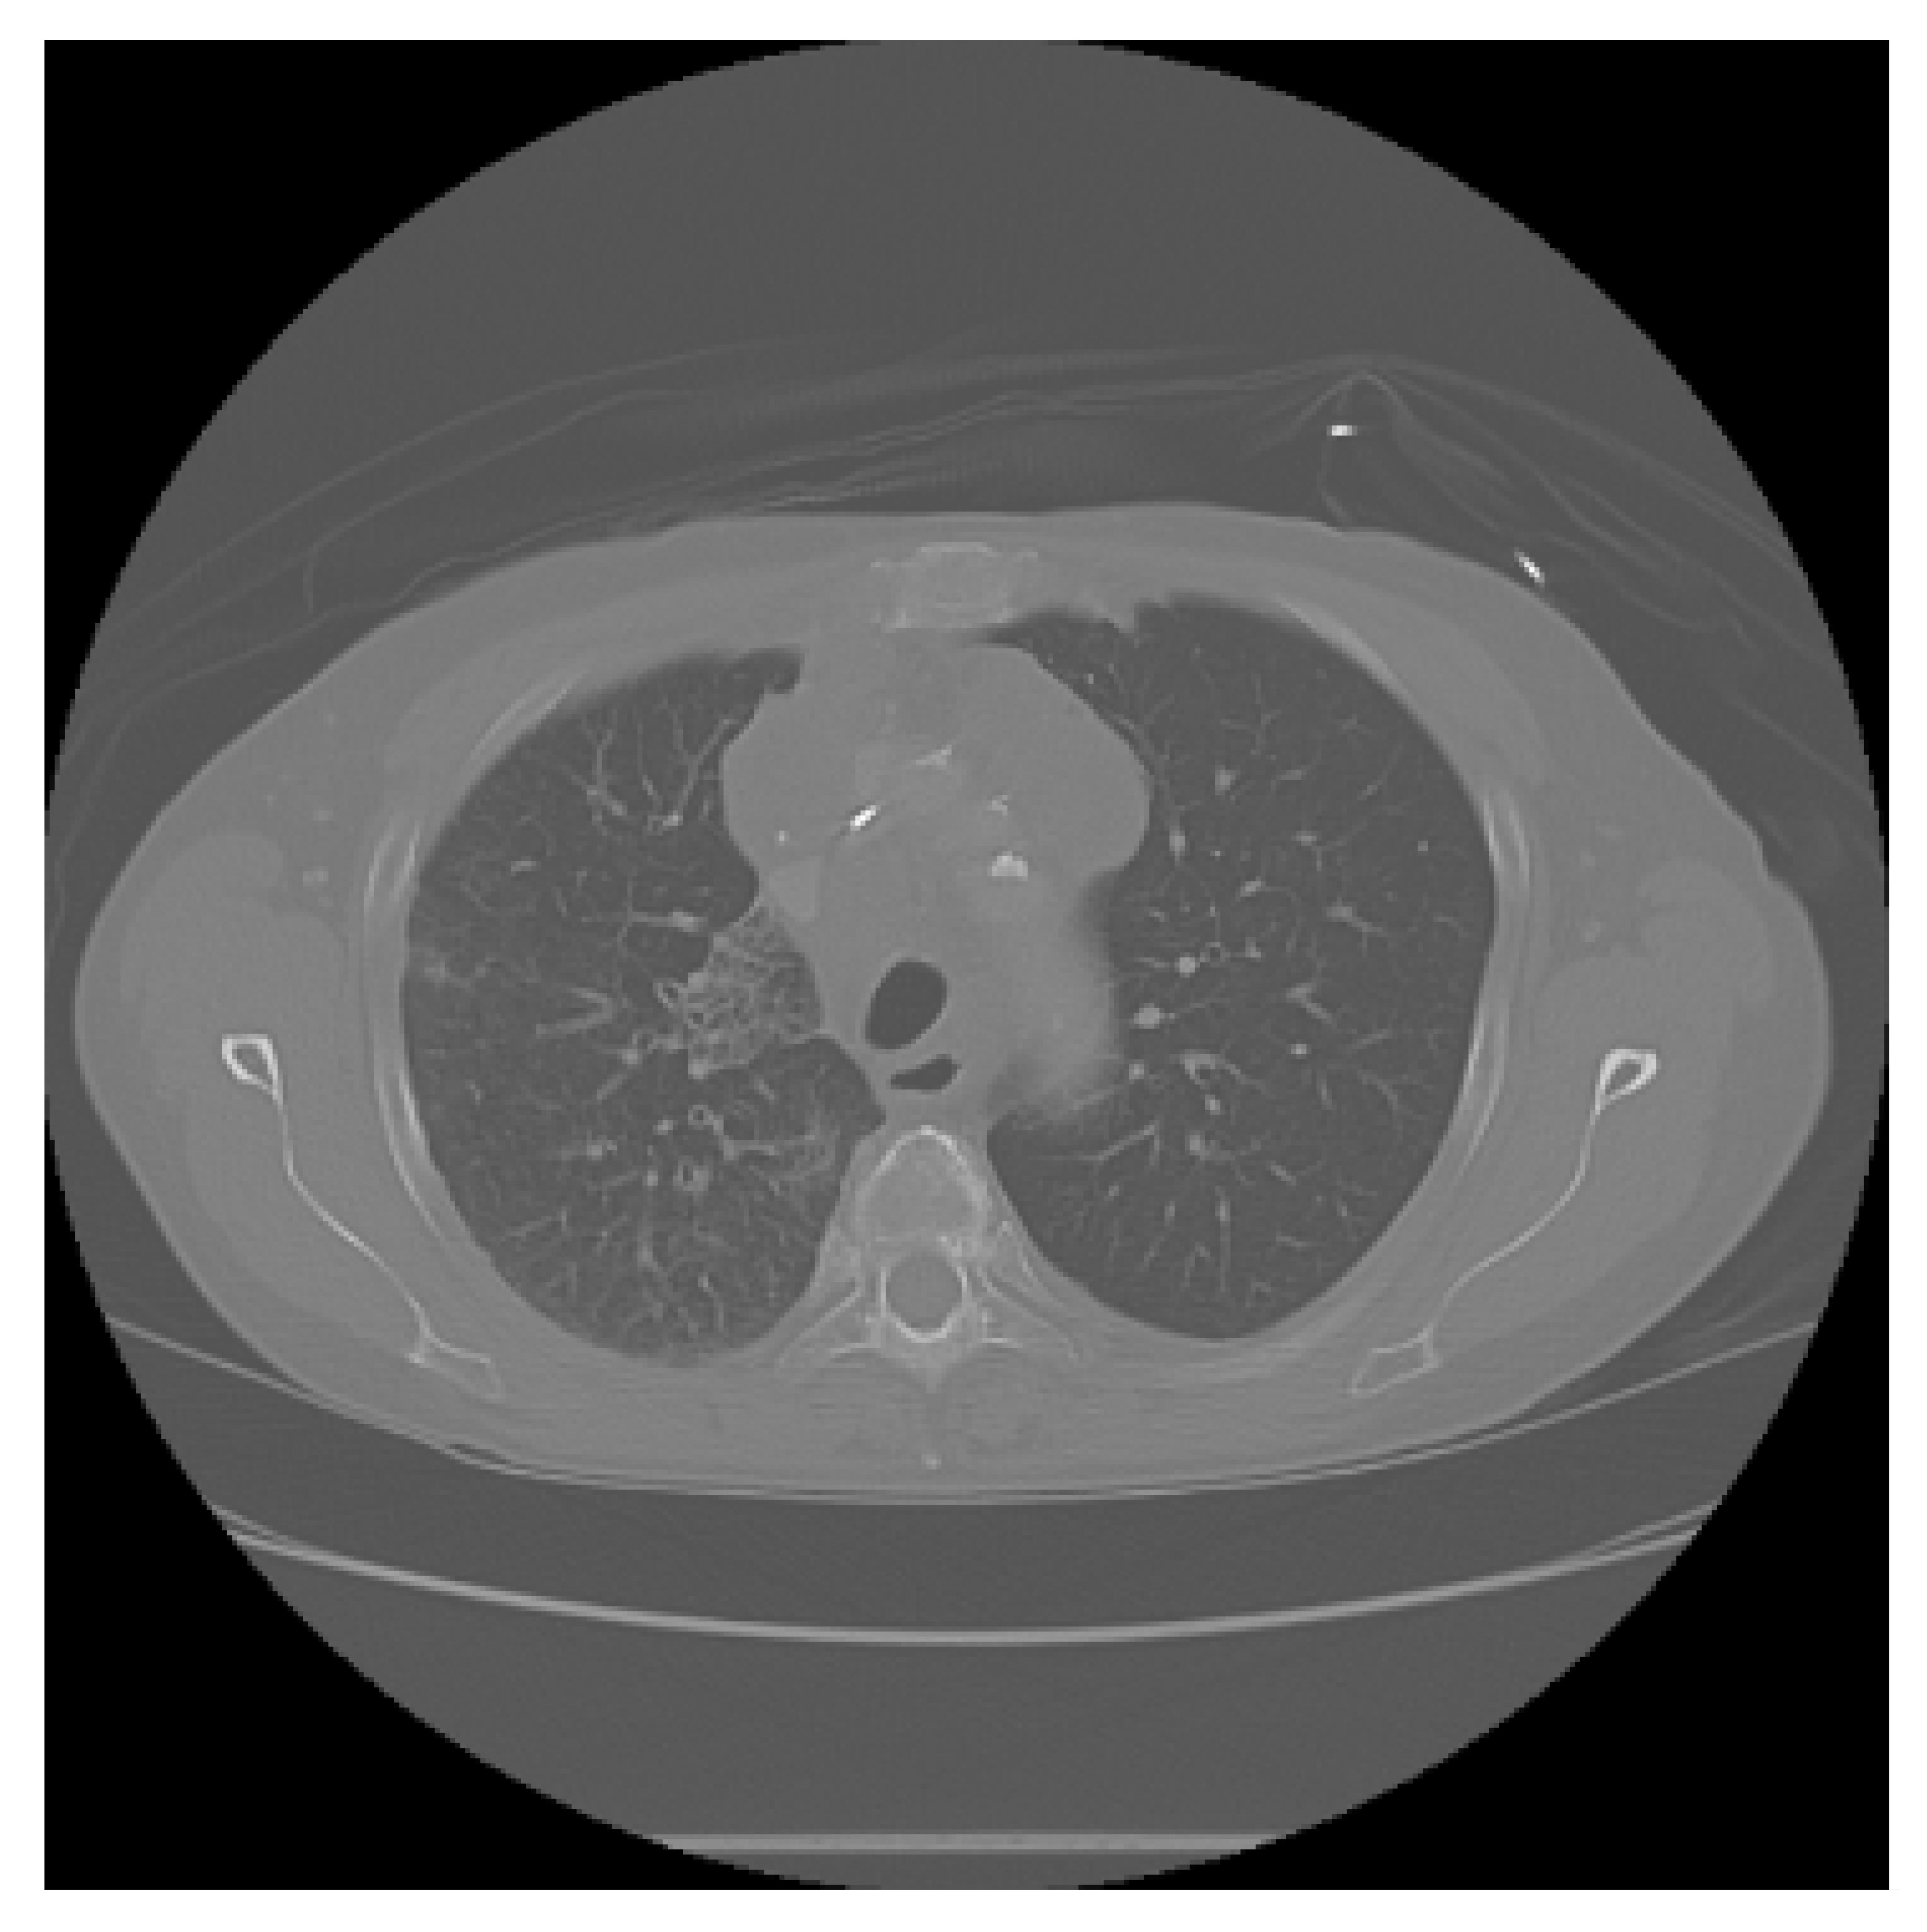

The APILungCancer interface provides intuitive functionality for loading and analyzing DICOM medical images. In the Load DICOM Images section, users can select and process CT scans for lung cancer evaluation. Once an image is loaded and analysis is performed, the software presents a visualization of the image along with the predicted probability of cancer (Table 7). Our study focused on lung cancer, including subtypes such as adenocarcinoma, squamous cell carcinoma, and small cell carcinoma. About 1000 training images and 300 test images from the CMB-LCA dataset were used to develop and validate the system.

In this example (Figure 5), the DICOM image 1-27.dcm from the test set was processed and the software calculated a cancer probability of 0.4267 (42.67%), indicating a high likelihood of malignancy.

Figure 5.

Determination of the probability of lung cancer. Example output of the system for the image 1-27.dcm, yielding a predicted probability of 42.67%, consistent with Table 7.

This value matches the result in Table 7, confirming the consistency of the predictions generated by the AI-based model integrated into the system.